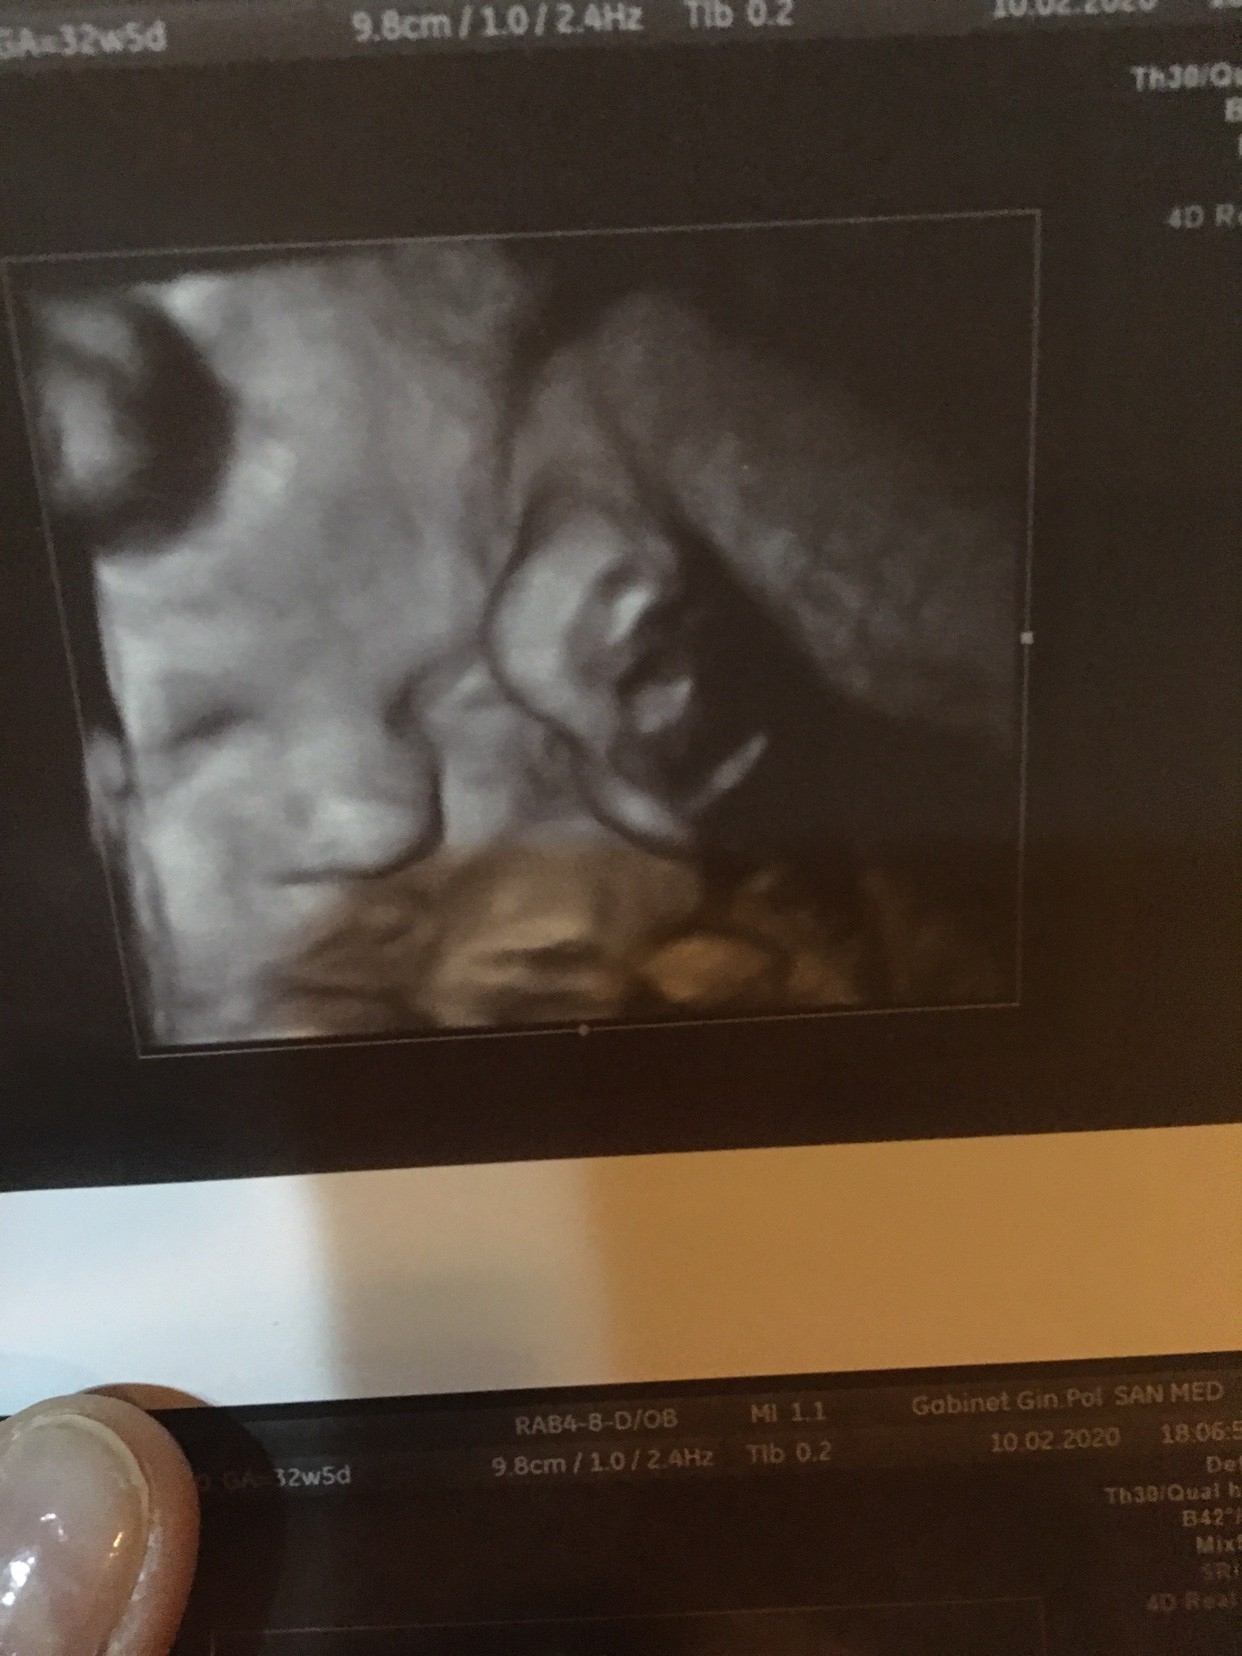

Jak zobaczyłam stopę koło głowy to się przeraziłam - ale podobno dzieci tak robiąZobacz załącznik 1078684